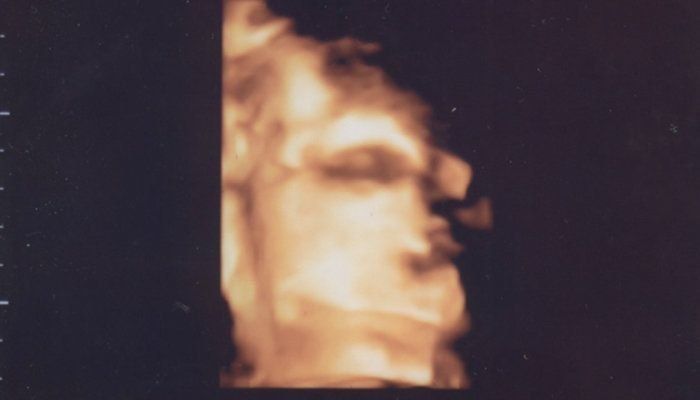

セイコさんの妊娠40週目のエコー写真 予定日ですが出てくる気配がありません

出てくる気全く無しの余裕の寝顔が撮れました。頭の大きさは依然9.4cm、おそらく最初に計ったのが大きかったのですかね。体重はといえば、いくらおおよそとはいえ、3570g!出てこられるのかと不安になります。